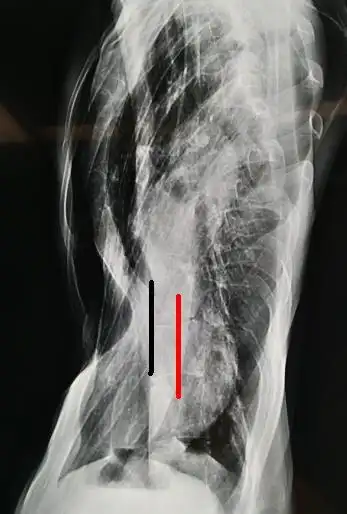

(x线图像,左侧胸廓塌陷,胸膜增厚,脊柱侧弯)术前查体:胸廓左右不对称

图4,脊柱侧弯,心脏位于左侧胸腔.